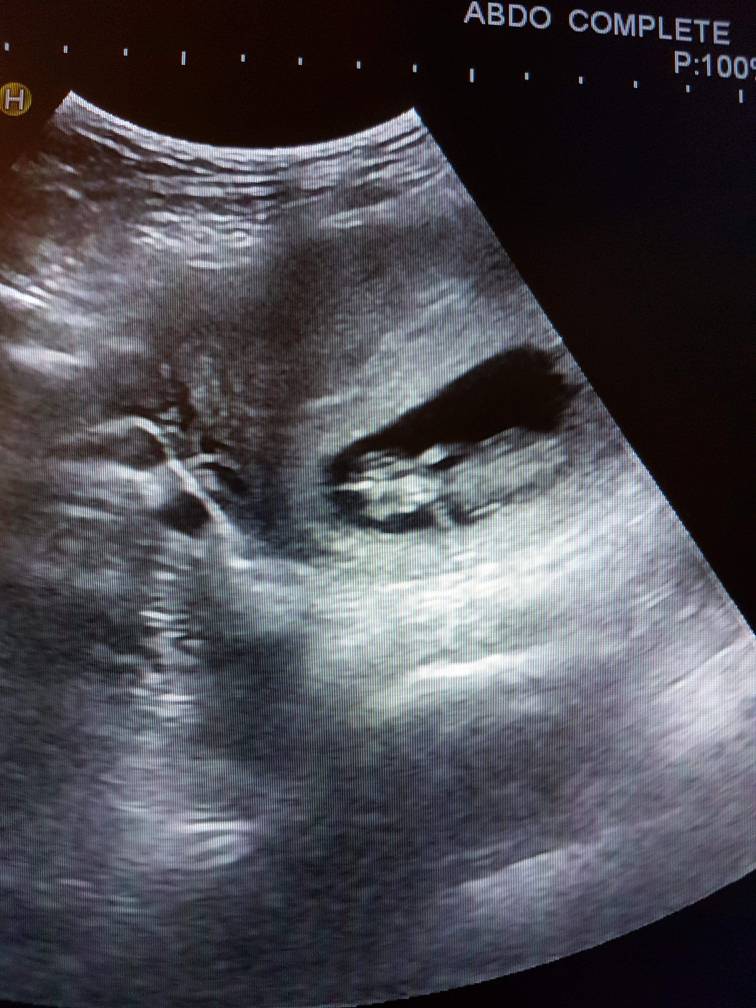

Jeg har vært på ultralyd idag, 9+5, og har fått se en sprellende liten minibaby med både armer og bein!Alt var bra og jeg spurte legen om hvordan sjansene var for at det skulle gå bra nå, og da svarte han 100%.

Han la til at han kunne selvsagt ikke forutsi noe, men siden babyen hadde riktig størrelse og beveget seg, hodet hadde riktig størrelse i forhold til kroppen, det var armer og bein, hjertet slo fint og fostersekken og eggstokkene så fine ut og det ikke var noen hevelse i nakken, så var det ingen grunn til å tro at dette ikke skulle gå bra. Jeg er så lettet! Beste dagen på evigheter!

Vis vedlegget 252882